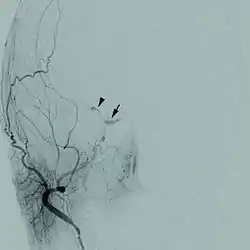

![]() تصوير الأوعية ناسور جيب كهفي تصوير الأوعية ناسور جيب كهفي | |